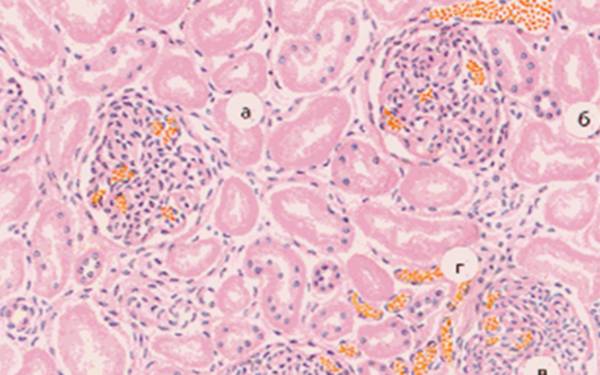

<center>На фото некротические измнения эпителиальных клеток извитых канальцев почек или острый тубулярный некроз — микропрепарат</center>

- Некроз эпителия извитых канальцев почки на микропрепарате и настоящем органе характеризуется повреждением клеток канальца нефрона. Обычно это заболевание развивается из-за воздействия на организм токсических веществ. Помимо этого, патология может появиться из-за нарушения притока крови к органам в результате воспаления, травмы, сепсиса или шока. Также прогрессу некроза эпителия канальцев почки могут служить оперативные вмешательства, травматические повреждения, механическое давление на органы или его канальцы, прием токсичных препаратов.

Микропрепарат №7 НЕКРОЗ ЭПИТЕЛИЯ ИЗВИТЫХ ПРОКСИМАЛЬНЫХ И ДИСТАЛЬНЫХ КАНАЛЬЦЕВ ПОЧКИ. ОКРАСКА ГЕМАТОКСИЛИН-ЭОЗИНОМ

Дистальные прокс канальцы без изменений. Эпителий и клубочки содержат ядра. Цитоплазма в сост коагуляции, в некоторых местах гомогенна. Наблюдается разрушение базальной мембраны (тубулорексис). Отмечается кариопикноз, кариолизис, плазморексис. Капилляры петли клубочков малокровны, а сосуды мозгового вещ-ва почки – полнокровны